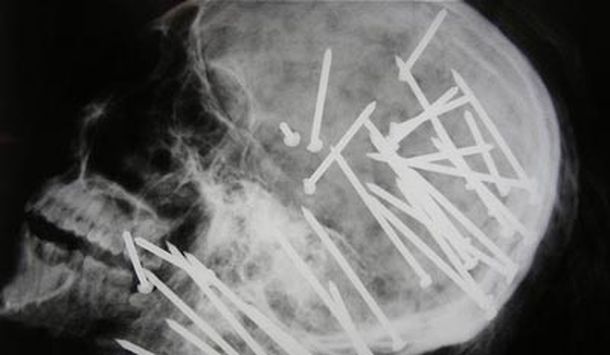

Con la ayuda de una pistola para clavar, alguien disparó 34 clavos en la cabeza y el cuello de Chen Liu, un inmigrante chino que vivía en el sur de Sydney, Australia. El cuerpo fue encontrado por dos chicos que le avisaron de inmediato a la policía.